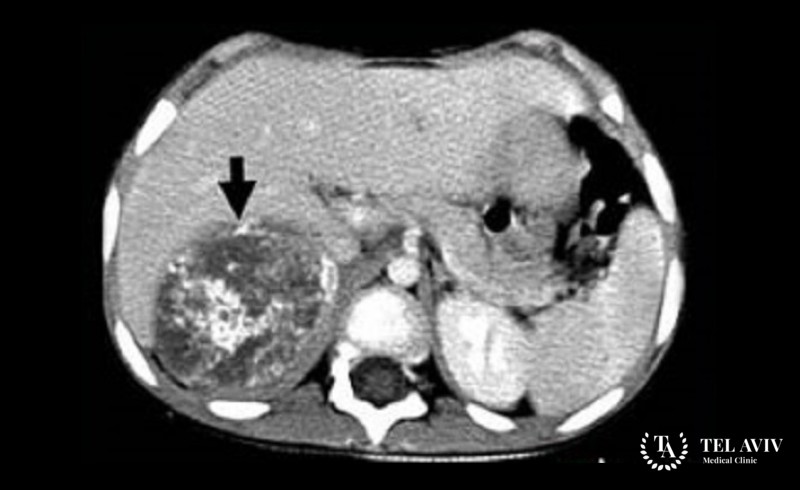

- CT scan.